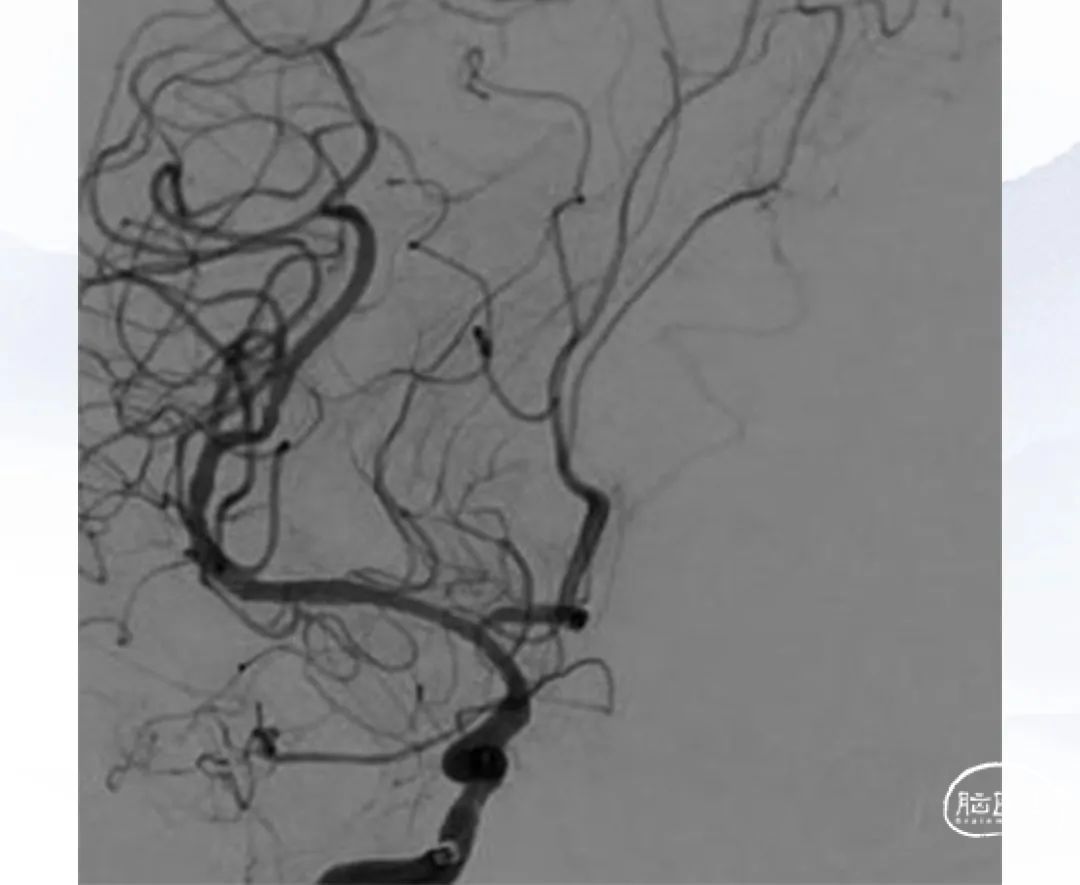

上海心玮医疗科技股份有限公司(股票代码:06609.HK)成立于 2016 年,公司致力于提高创新医疗技术的可及性,守护生命健康。六年时间,心玮医疗在神经介入领域开拓性地打造了国内首个卒中治疗及预防一站式解决方案,拥有从急性缺血性卒中和神经血管狭窄治疗、缺血性卒中预防、出血性卒中治疗到介入通路器械的全产品管线,申请专利超过 100 项,产品年产能超过 15 万件,销售渠道覆盖国内超过 30 个省(含直辖市和自治区)的 1400 多家医院。